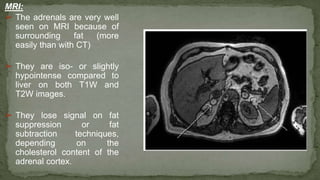

➢ The adrenals are very well

seen on MRI because of

surrounding fat (more

easily than with CT)

➢ They are iso- or slightly

hypointense compared to

liver on both T1W and

T2W images.

➢ They lose signal on fat

suppression or fat

subtraction techniques,

depending on the

cholesterol content of the

adrenal cortex.